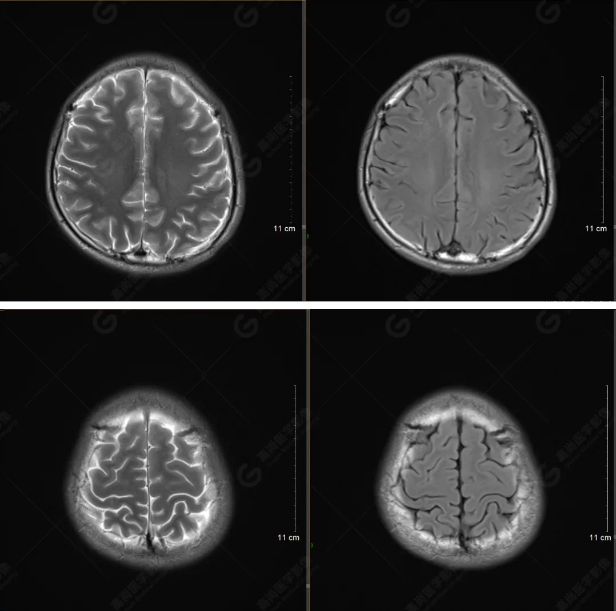

(左側(cè)為薄層原始圖像,右側(cè)為后處理5mm圖像)

SWI序列影像表現(xiàn)及診斷

左側(cè)額底及左側(cè)顳葉內(nèi)見多發(fā)斑點狀極低信號影??紤]額顳葉多發(fā)腦挫傷伴微出血、含鐵血黃素沉著,左側(cè)乳突骨折、乳突內(nèi)積血。討論:1、SWI利用不同組織間磁敏感的差異成像并將其放大,通過檢測病灶中的靜脈分布、出血灶和礦物質(zhì)沉積等,有效改善了相關(guān)疾病的診斷,主要應(yīng)用于中樞神經(jīng)系統(tǒng)。2、根據(jù)磁距圖像和相位圖像表現(xiàn),對于鑒別顱內(nèi)出血及鈣化有一定程度的價值,用于彌補(bǔ)MRI對鈣化顯示的不足。